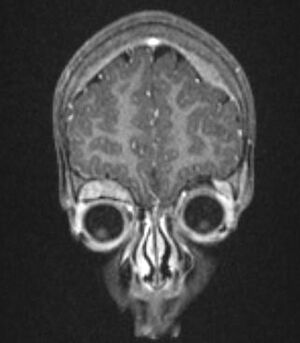

في الفحص المجهري ، توصف خلايا الورم عادةً بأنها صغيرة ، مستديرة وأزرق ، ويمكن رؤية أنماط وردية ( هومر رايت الوردية الزائفة) . ( هومر رايت الوردية الزائفة) هي خلايا سرطانية حول اللبد العصبي ، لا ينبغي الخلط بينها وبين الوريدات الحقيقية ، وهي خلايا ورمية حول تجويف فارغ.[26] كما أنها تختلف عن الأشكال الوردية الكاذبة للورم البطاني العصبي الذي يتكون من الخلايا السرطانية مع البروتين الحمضي الليفي الدبقي (GFAP) - عمليات إيجابية تتناقص نحو الأوعية الدموية (وبالتالي مزيج من الاثنين)..[27] يستخدم اختصاصيو علم الأمراض مجموعة متنوعة من الصبغات الكيميائية النسيجية المناعية لتمييز اورام الخلايا البدائية العصبية عن المقلدات النسيجية ، مثل الساركوما العضلية المخططة ، وساركوما إوينغ ، ولمفوما ، وورم ويلمز .[28]